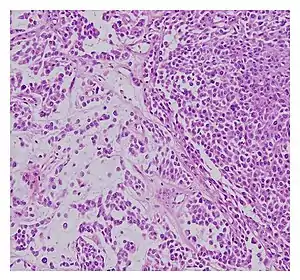

![]() | |

| Histopathological examination of malignant chondroid syringoma | |

Histologically, these malignant mixed tumours have epithelial and mesenchymal components and are very large, nodular, circumscribed, and nonulcerated.[11] They are morphologically identical to pleomorphic adenoma and have a female predilection.[4] They range from developing deep dermal to subcutaneous nodules and metastasise at a very high rate.[4][8] Malignant mixed tumours can emerge "de nova or more rarely develop from a cartilaginous syringoma."(IADVL, 2004)[11]